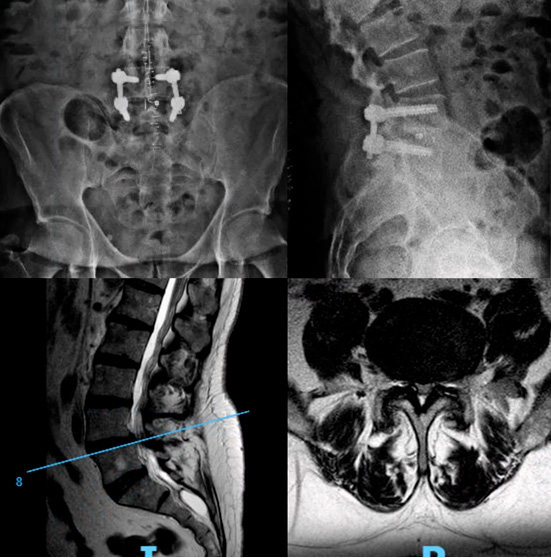

La artrodesis lumbar es una intervención quirúrgica que consiste en fusionar dos o más vértebras de la columna lumbar, eliminando el movimiento entre ellas para reducir el dolor y mejorar la estabilidad. Aunque siempre existe la preocupación de quitar movilidad, siempre hay que pensar que el segmento que se elimina está enfemo. Por ello, esto no suele traducirse en una pérdida real de movimiento percibida por el paciente.

La artrodesis puede asociar una técnica de fusión intersomática, esto quiere decir añadir un gesto que provoque una fusión en el disco que separa los cuerpos vertebrales. Existen diferentes tipos de técnicas, como ALIF, TLIF, PLIF, OLIF o XLIF que dependerán de la vía utilizada. La necesidad de este gesto asociado dependerá de cada caso. Estas técnicas han demostrado mejorar la tasa de fusión y modificar la lordosis segmentaria.

La artrodesis lumbar se suele considerar como una opción terapéutica tras agotar tratamientos no invasivos. Normalmente, este procedimiento es una cirugía abierta, más extensa, aunque en algunos casos puede realizarse mediante abordajes mínimamente invasivos, con incisiones pequeñas y menor daño muscular. La elección depende del tipo de patología y del paciente.